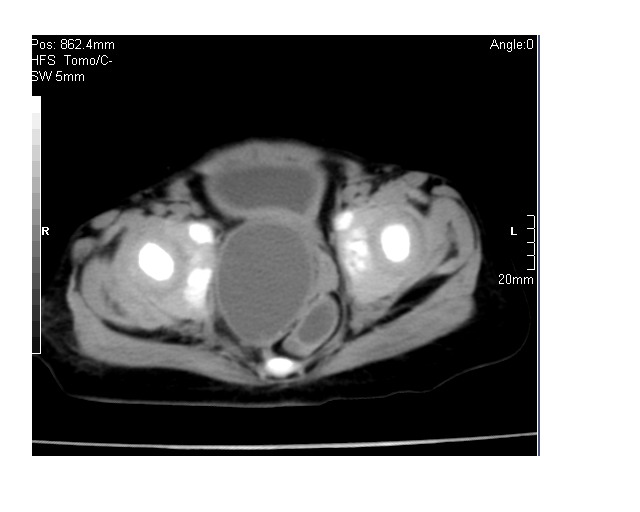

以下是引用lkc8963在2008-3-16 12:49:00的发言:[br]盆底巨大混杂密度肿块,富含多种组织成分包括脂肪/液体/软组织/钙化,边界清楚,向前压迫肠管及膀胱,向后突入骶尾部皮下脂肪层,首先考虑畸胎瘤,诊断时需要与脊柱裂/囊性淋巴管瘤等区别。